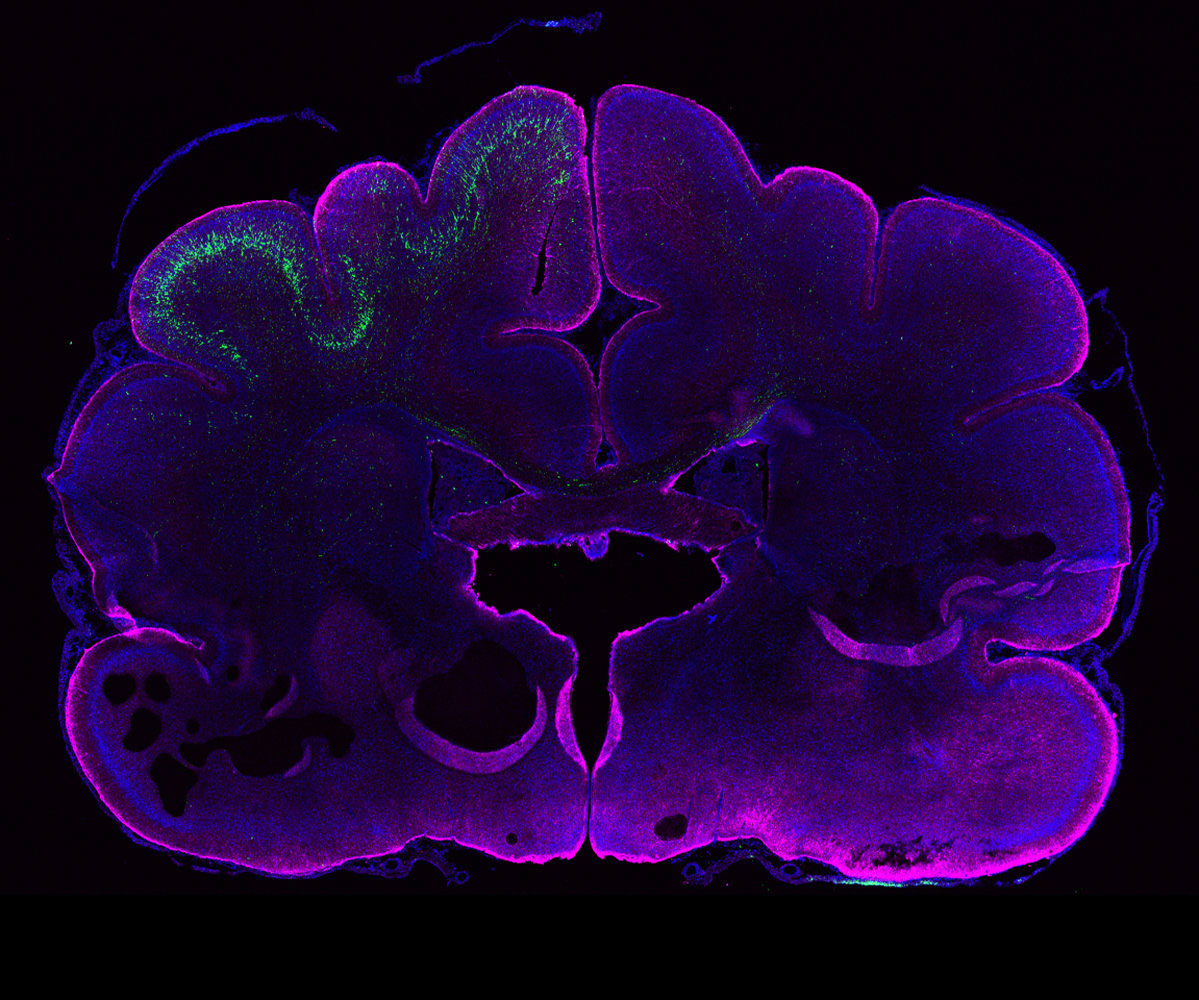

유전자 이식 후 101일이 지나 확인해본 원숭이의 뇌는 신피질이 더욱 커졌고, 인간과 같은 수준의 주름이 생겼으며, 신경 세포를 만들어내는 세포의 종류가 급격히 증가했습니다.